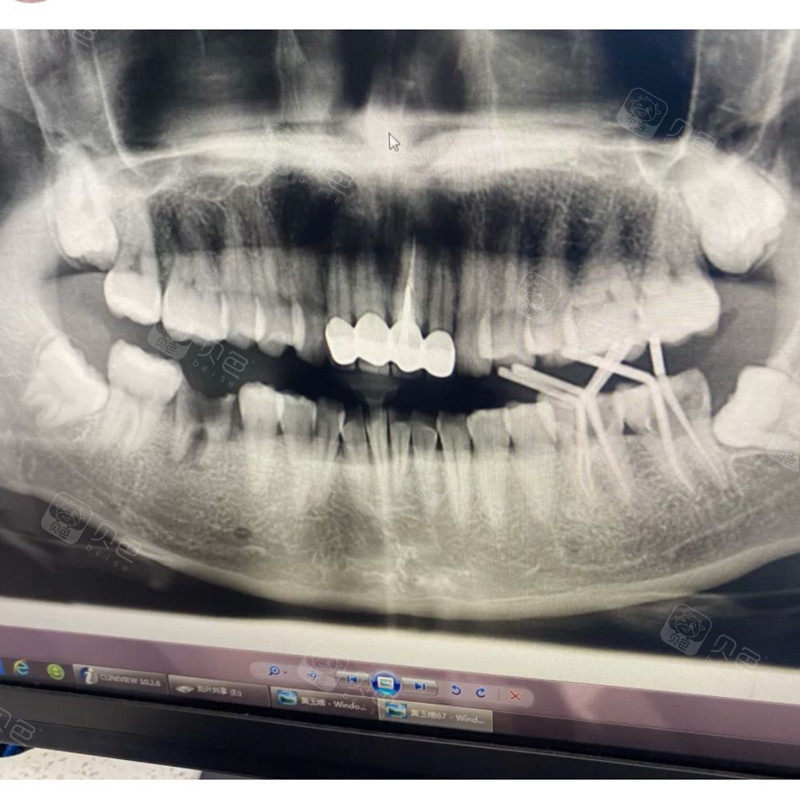

蛀牙牙片

蛀牙牙片,正常牙齿和蛀牙图片

智齿蛀牙各种问题都聚齐了我好惨

蛀牙,发炎了,已经拍了牙片了,帮忙看下.

全景牙片